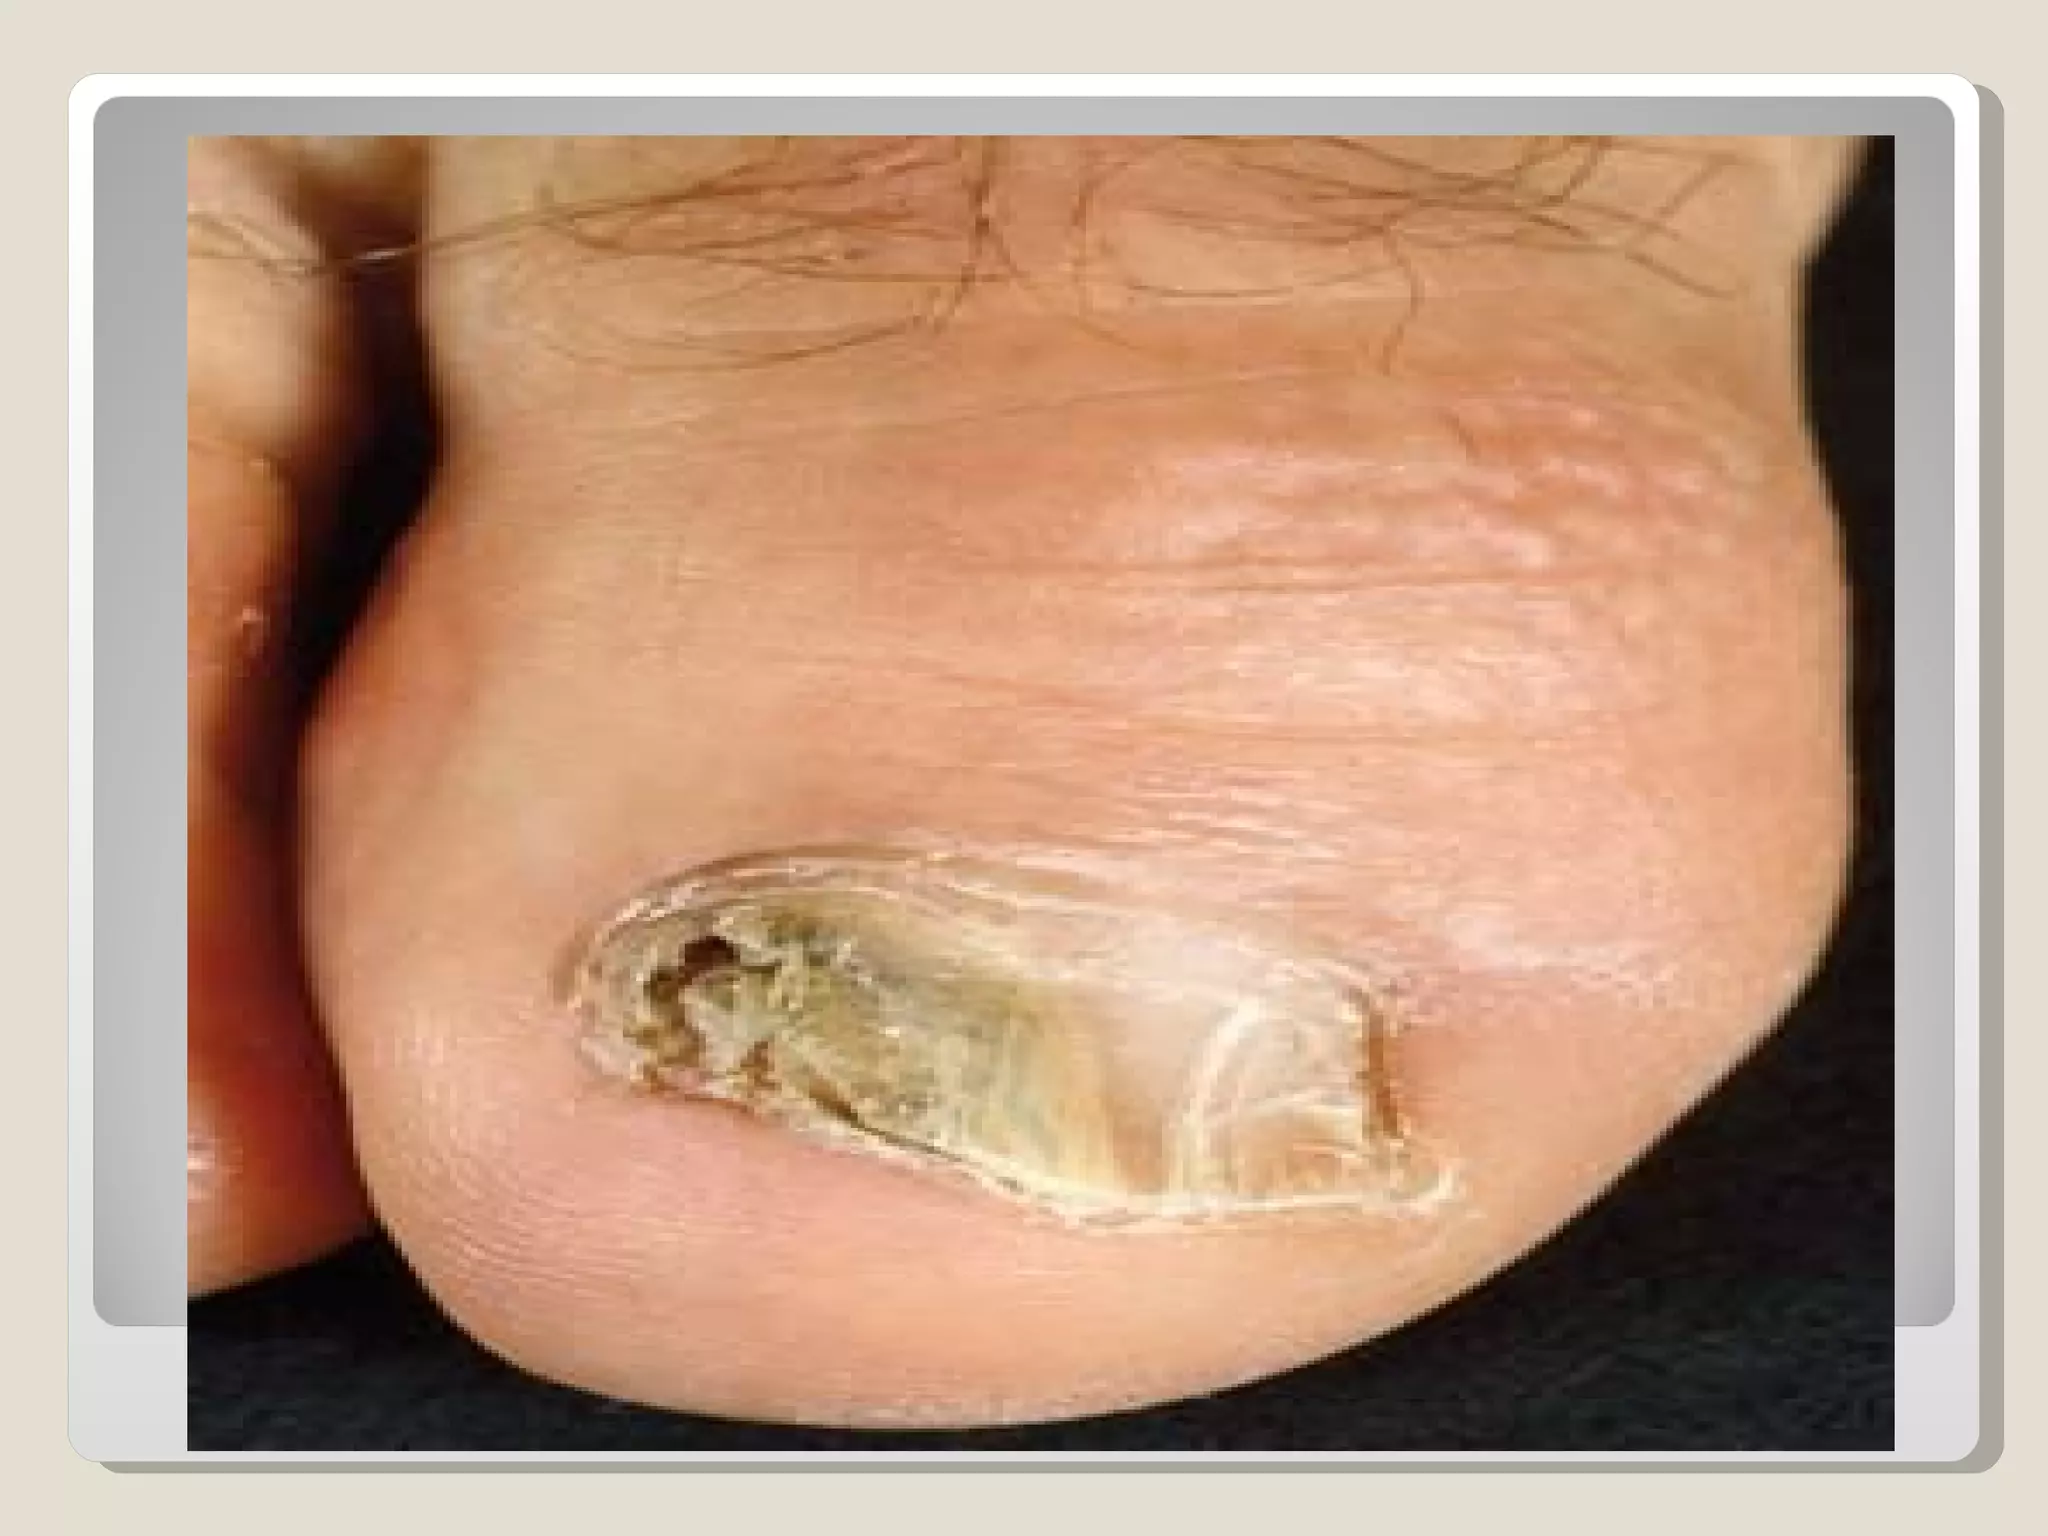

7. Tinea Unguim:

Fungal infection of the nail of the hand.

    Nail: Paronychia.